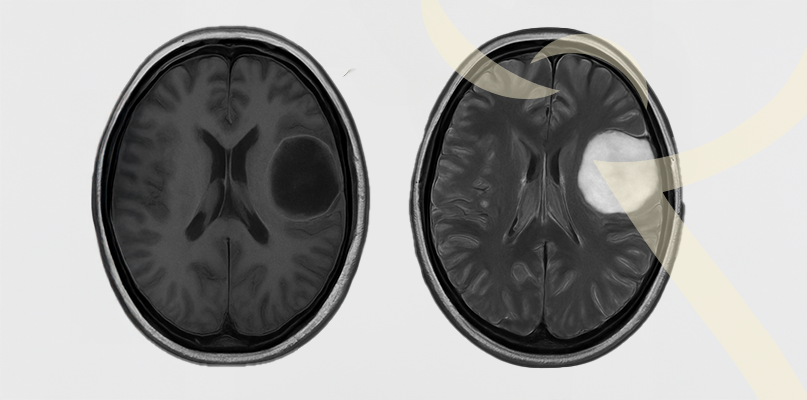

Gliomas – tipos, sintomas e opções de tratamento

Os gliomas são tumores que se originam nas células da glia, responsáveis por dar suporte aos neurônios. Eles podem variar de benignos a malignos, sendo o glioblastoma a forma mais agressiva.

O diagnóstico é realizado por ressonância magnética e biópsia.